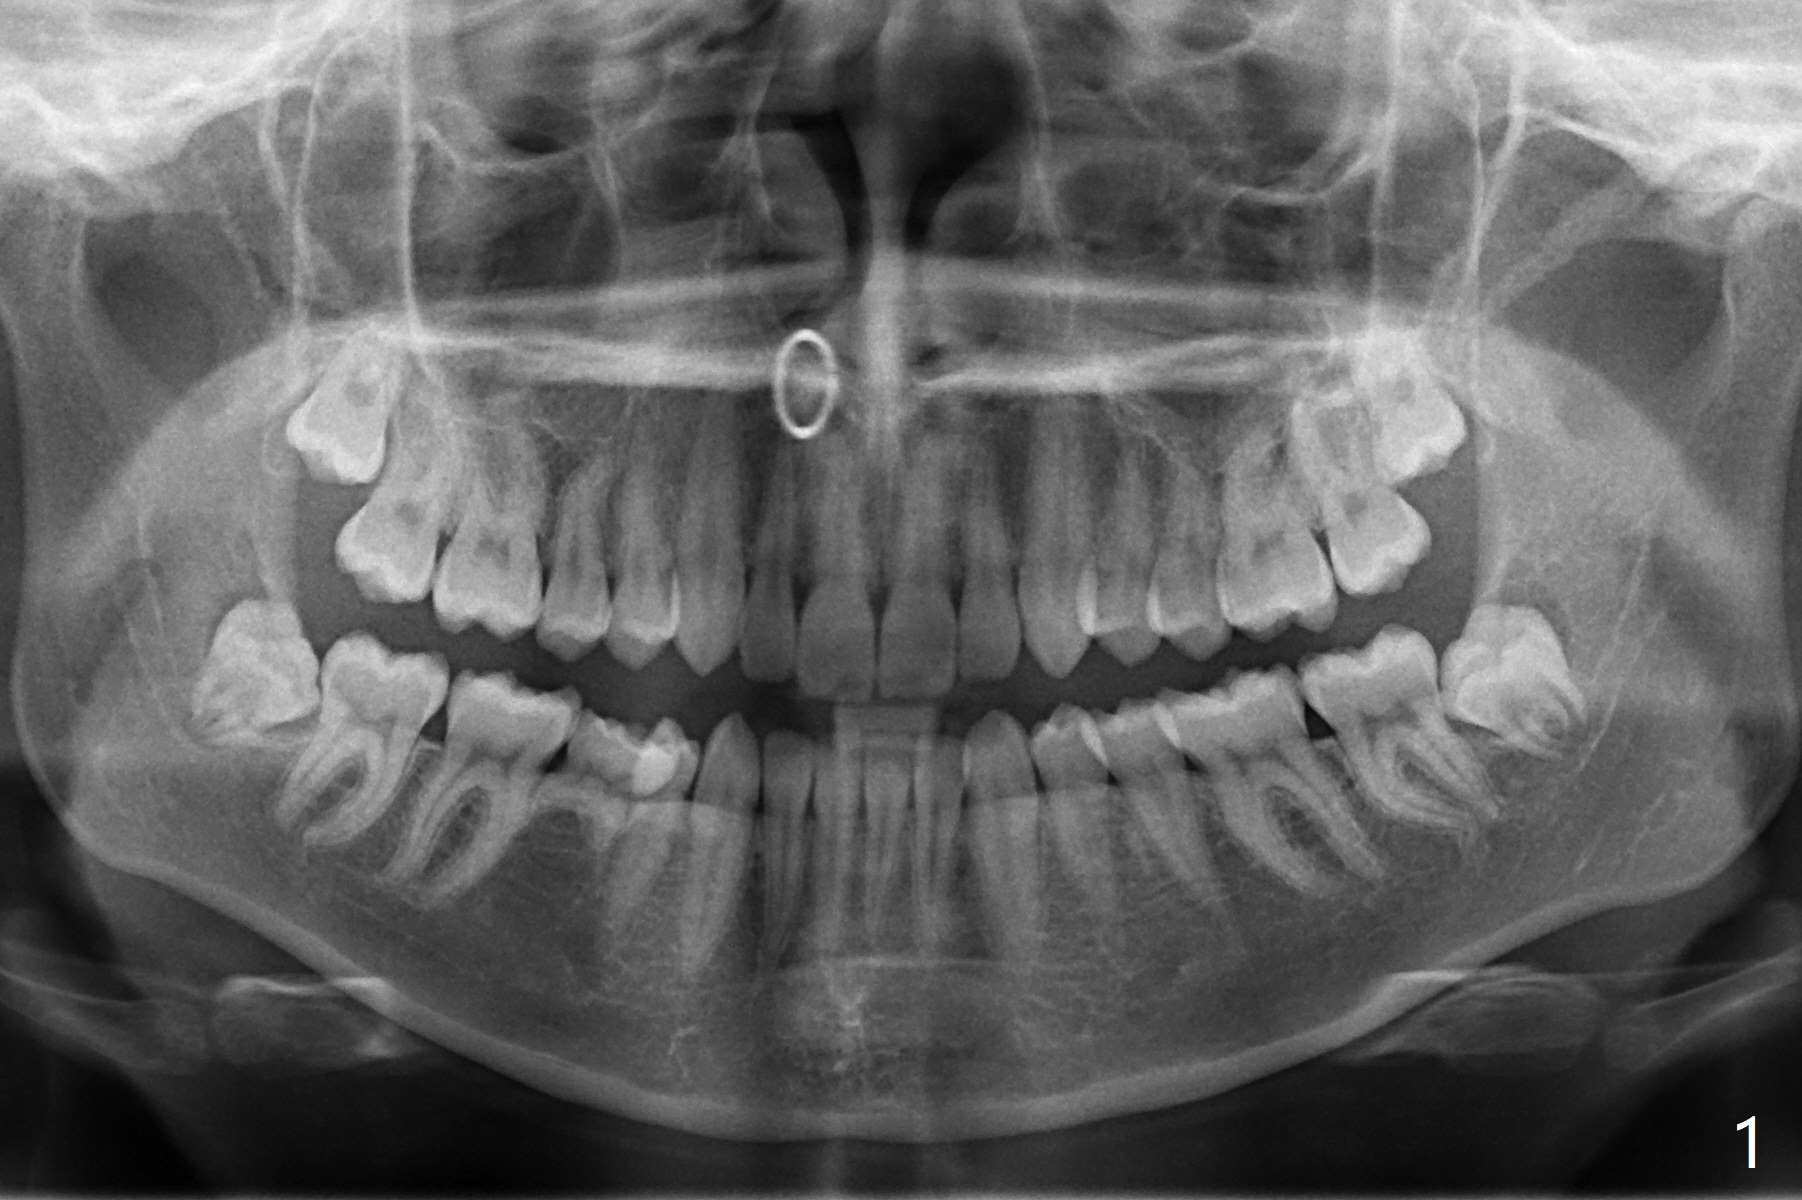

A 21-year-old nervous woman wants to have 4 of the 3rd molars extracted (Fig.1). To prevent dry socket, place collagen plug at #17 and 32. Take panoramic 4 Bitewings postop and preferably preop, since Fig.1 was taken on January 1, 2018 and #17 and 32 are close to the Inferior Alveolar Canals. In fact Osteogen plug is placed at #16 and 17 due to apparently severe bony defect affecting the neighboring teeth, while Collagen plug at #32.